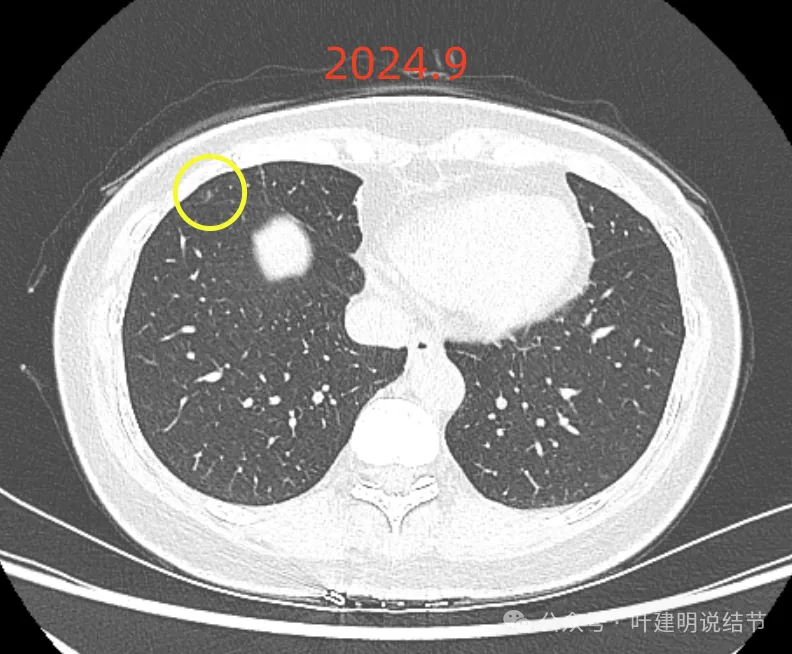

最后来看2024年9月,也就是叫停手术后2整年之后复查的情况:

仍说不上有明显进展,如果将这几次的放在一起来对照,就会更加直观:

病灶基本上没有明显变化。当然不必过于在意具体大小有没有几毫米的差别,也不必在意具体CT值有几十或百把的区别,微细的差别不影响临床决策,也就是说改变都不足以让肉眼发现的,怎么会影响预后呢!

我看了你2022年2月时的片子,以及某医院建议你手术说有进展时的2022年5月时的片子和2023年8月复查时的片子,再对比2024年9月时的影像,总体上明显点的病灶仍是这三处。首先均仍是纯磨,有的似有微血管进入或穿行,但磨玻璃成分密度很淡,而且大小无明显进展。至于右上病灶是否有缩小好转,感觉上右上的与右中叶的都略显淡了点,我怀疑还是扫描条件不一的关系,本身又是非常小而淡的病灶,可比性稍差,并不能说明必是有吸收好转。但肯定说不上有进展,风险仍是低的,半年或一年复查随访(个人倾向可以年度复查)总归不至于会耽误病情。意见供参考!